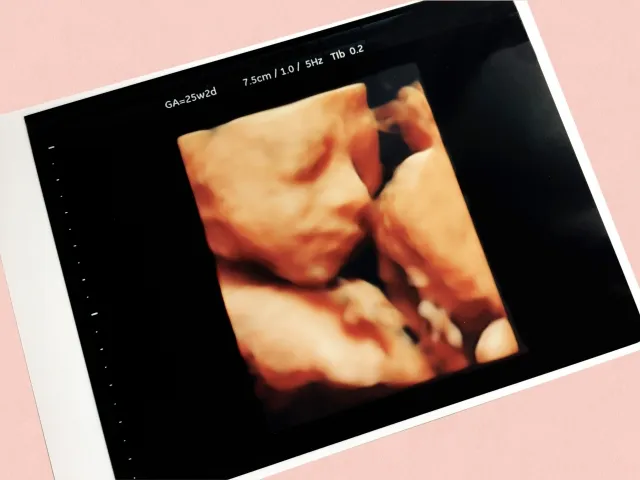

4Dエコーとは、赤ちゃんの姿を立体的な映像でとらえ、さらに「時間の流れ(=動き)」を加えてリアルタイムで確認できる超音波検査です。従来の2Dエコーでは平面的な白黒画像が中心で、赤ちゃんの向きや位置によっては表情や細かな動きが分かりにくいこともありました。

これに対し4Dエコーでは、赤ちゃんの顔立ちやしぐさがより直感的に捉えられ、妊娠期の体験をより豊かなものにしてくれます。

例えば、手足を伸ばしたり縮めたりする様子、指をしゃぶるしぐさ、あくびをするような表情など、赤ちゃんの自然な動きが記録として残せます。こうした姿を目にすることで、赤ちゃんの存在をより身近に感じられ、ご夫婦やご家族で喜びを共有する大切な時間にもつながります。

4Dエコーは妊娠のどの段階でも撮影自体は可能ですが、特に鮮明に映りやすい時期として 妊娠20〜32週頃 が推奨されています。

この時期は赤ちゃんの体つきがしっかりしてきて、顔のパーツや身ぶりが見えやすく、4Dエコーならではの立体的な映像が得られやすいためです。

• 25〜30週ごろ

顔の輪郭がはっきりし、しぐさや表情が最も分かりやすいタイミングです。表情が柔らかく、自然な姿が見えることも多く、この時期に4Dエコーを希望される妊婦さんが特に増えます。